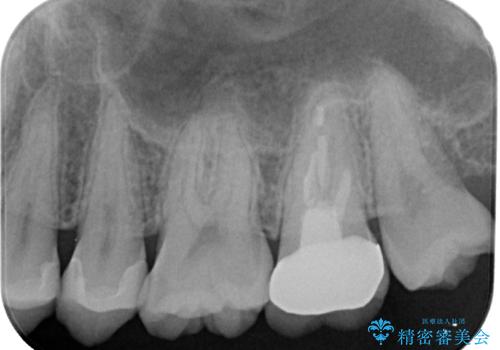

- すごく前に治療したレジンがざらつくので治療したいとのことで来院された患者様です。十年ほど前に根管治療を行っており、症状は特に何もない状態でした。根管治療を行っている歯は咬合力に対して鈍くなり破折しやすくなるため、最終的には被せものによる補綴治療を行う必要があります。

ラバーダム防湿下でコンポジットレジンを除去しファイバーコア築造を行い、オールセラミッククラウンに適した形に整えました。

歯と歯茎の間に圧排糸と言われる糸を入れてシリコーン印象材にて型どりをしました。